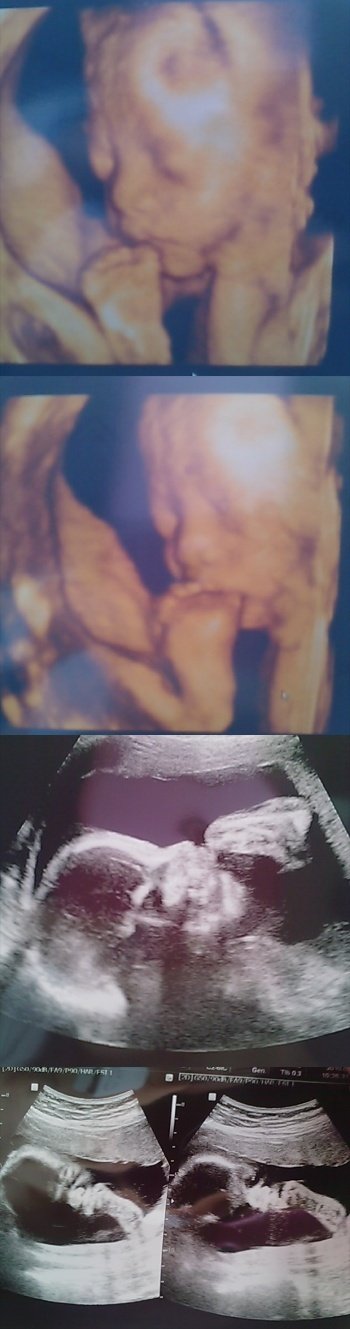

25주2일때 뱃속에있을떄 초음파사진 ㅋㅋㅋ

발빨고있는사진ㅋㅋㅋㅋㅋㅋㅋㅋㅋㅋㅋㅋㅋㅋ

우리 백호귀엽져

세상에서 단하나뿐이 없어여 발빨고있는사진@.@ㅋㅋㅋ

아빠ㄱ ㅏ전직축구선수엿어서 그런지 발빨고있네염ㅋ_ㅋ

산부인과에서 아가공모전할때 이거 공모해서 개성상탓어요@@@

상금과 상품 상장 그리고 액자받아뜨래져?